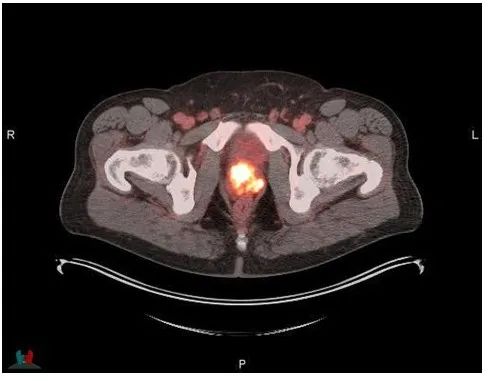

▲前列腺摄取的Posluma的PET/CT图像(图片来源:参考资料[1])

Posluma是一种优化的PSMA靶向分子,可以与表达PSMA的细胞结合并被其内化,例如经常过表达PSMA的前列腺癌细胞。通过放射性同位素氟-18(18F)的标记,使得此分子能够对前列腺和已有前列腺癌细胞扩散的其他身体部位进行PET成像。18F放射性同位素所产生高质量的PET影像有助于有效检测疾病,使广泛患者受益。